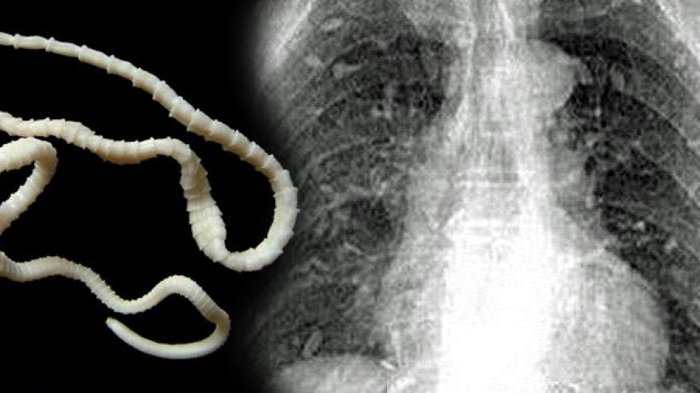

Ngeri, Hampir di Seluruh Tubuh Pria Ini Ditemukan Banyak Cacing Pita, Penyebabnya Sepele!

Bagaimana bisa ditemukan banyak cacing pita di hampir seluruh tubuh pria ini?

Nah, seorang pria yang berasal dari Tiongkok mengalami insiden ini.

Awalnya dia merasakan sakit perut dan gatal di sekujur tubuh.

Kemudian, pria yang tak disebutkan identitasnya itu pergi ke dokter.

Setelah dilakukan pemeriksaan dan scan hasilnya sangat mengerikan.

Terdapat cacingpita hampir di seluruh tubuh pria ini.

Nah, akibat terinfeksi cacing pita, pria ini dirawat di sebuah rumah sakit di bagian Timur Tiongkok.

Dikutip Grid.ID dari Dailymail, menurut penelitian menunjukkan infeksi ini karena pria telah mengonsumsi terlalu banyak sashimi.

Sashimi yaitu irisan ikan mentah yang berasal dari Jepang.

Dokter yang menanganinya percaya jika ikan yang dikonsumsi itu telah terkontaminasi.

Sementara kasus seperti ini juga meningkat akibat sanitasi di suatu daerah kurang baik.

Seorang peneliti juga mengungkapkan popularitas sushi dan sahimi meningkatkan risiko infeksi cacing pita di tubuh manusia.